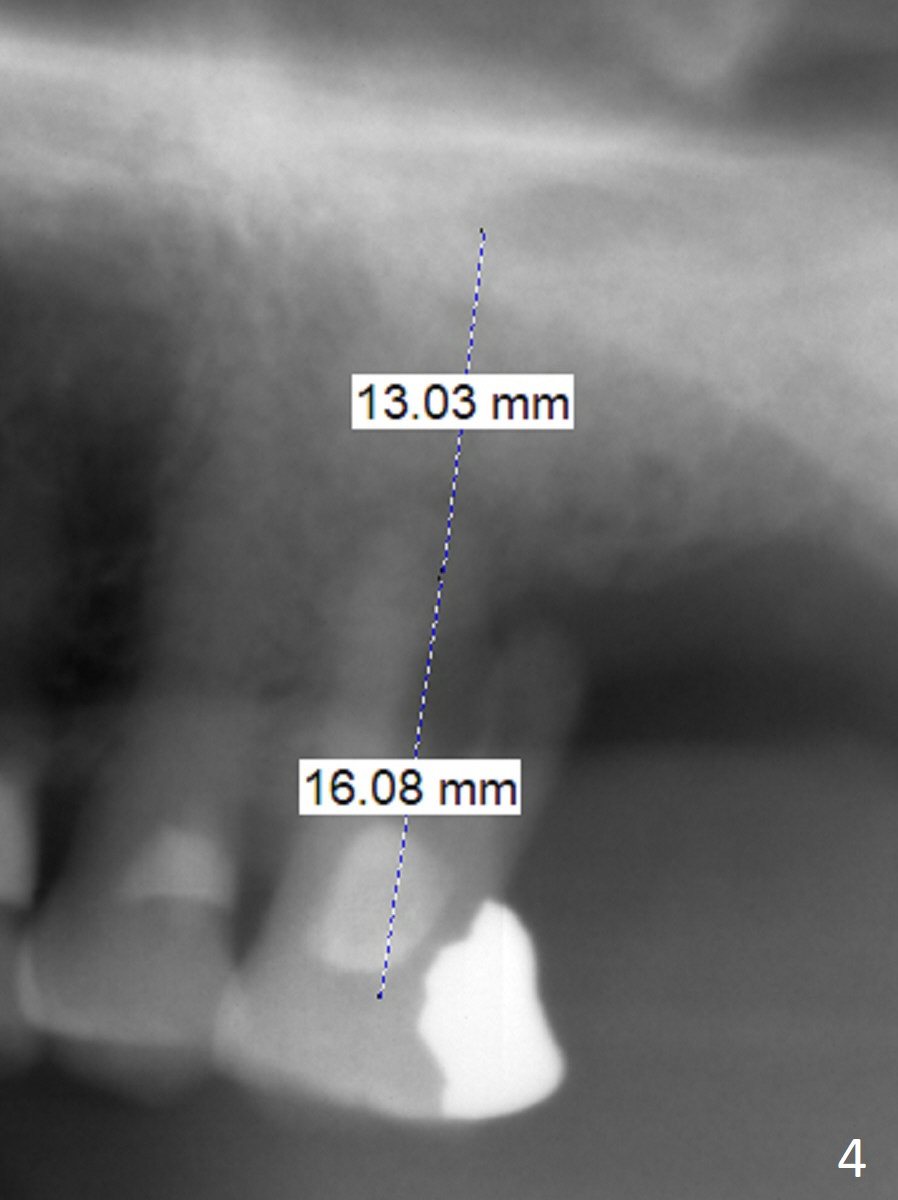

A 88-year-old man cannot masticate well on the left side because of the loose tooth at #14 with severe gingival recession buccal (Fig.1) and palatal (Fig.2 P). An implant will be placed in the septum; the peripheral defects of the sockets will be covered by PRF (x2) before bone graft. Initial depth of osteotomy will be 11 mm (Fig.3) with the implant length being 13 mm. Because of severe vertical bone loss, a mill abutment is expected (Fig.4). In fact CT shows the buccopalatal bone is wide. Use IS implant if it arrives. But cementation abutments are not available. A temporary abutment may be used. The patient is nervous about PRF.